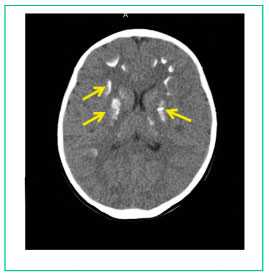

Компьютерная томография головного мозга - КТ-картина множественных кальцинатов в веществе мозга (синдром Фара) (рис. 4).

Рисунок 4

Множественные кальцинаты в веществе головного мозга (желтые стрелки).